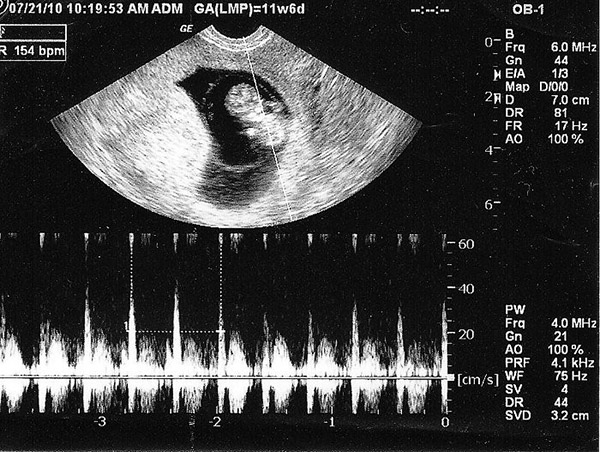

Theo thể trạng của mẹ và tốc độ phát triển của bé cũng khác nhau. Thông thường, khoảng từ tuần thứ 7 là mẹ đã có thể nghe thấy nhịp tim của bé thông qua siêu âm. Cũng có nhiều trường hợp tim thai đã xuất hiện ở tuần thứ 5, thứ 6 của thai kỳ, thậm chí là đến tuần thứ 10 mới có thể nghe thấy nhịp đập của bé.

Đến tuần thứ 12 của thai kỳ, tim bé được xem như đã hoàn thiện và cs thể thực hiện chức năng của nó là vận chuyển máu. Đến tuần thứ 14, nhịp đập của bé sẽ mạnh mẽ và rõ ràng hơn. Sang đến tuần thứ 16, mỗi ngày tim bé có thể bơm lượng máu lên đến 14 lít.

Đến những tuần tiếp theo, tim bé sẽ càng phát triển về kích thước lẫn khối lượng. Thông thường nhịp đập của bé vào khoảng 120 – 160 lần / phút, vào những lúc vận động nhiều có thể lên tới 180 lần / phút lớn gấp đôi nhịp đập của người bình thường.